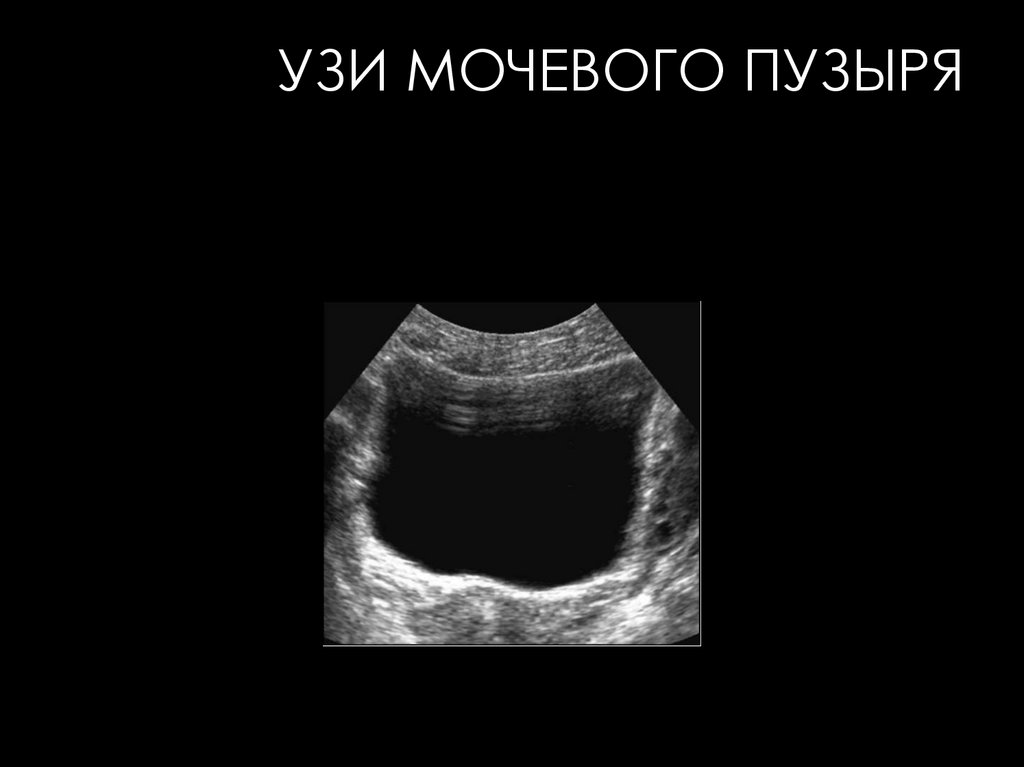

УЗИ МОЧЕВОГО ПУЗЫРЯ

• Пустой пузырь не дает отчетливого изображения как

орган и потому вообще не подлежит оценке.

• Обязательным условием получения эхографического

изображения мочевого пузыря является его наполнение

до физиологического объема, т. е. до появления первых

позывов на мочеиспускание.

• В поперечном сечении при адекватном наполнении

неизмененный мочевой пузырь обычно имеет вид

анэхогенного прямоугольника, трапеции или овала; в

продольном сечении - овоидную форму

25.